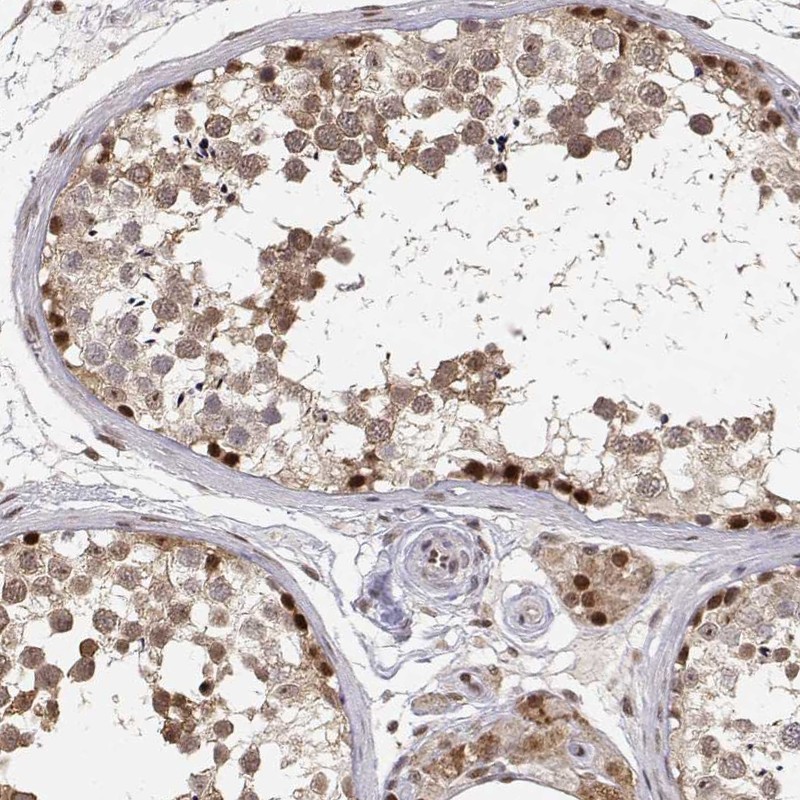

Immunohistochemistry analysis in human testis and pancreas tissues using Anti-BRCA1 antibody. Corresponding BRCA1 RNA-seq data are presented for the same tissues.